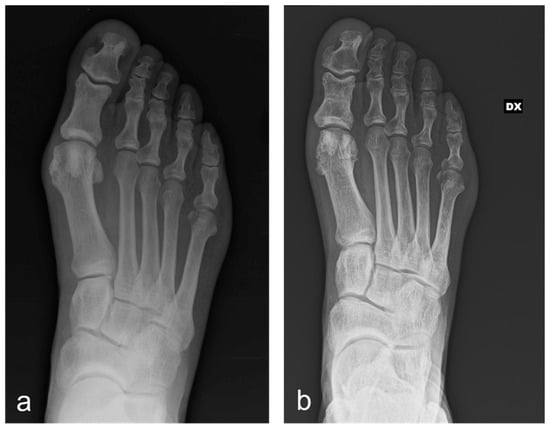

According to our institutional protocol, routine X-rays in anterior-posterior, latero-lateral and sesamoid views were obtained before surgery, immediately after surgery, at 1 month and 3 months post-surgery (all weight-bearing except for the immediate postoperative one) (Figure 1).

Figure 1. A 71-year-old man having undergone percutaneous Reverdin–Isham osteotomy, lateral release and Akin osteotomy for moderate HV correction: antero-posterior radiographic images at preoperative period (a) and 3-month follow-up (b), showing the complete healing of the osteotomies and the correction of the deformity. (DX: right foot).